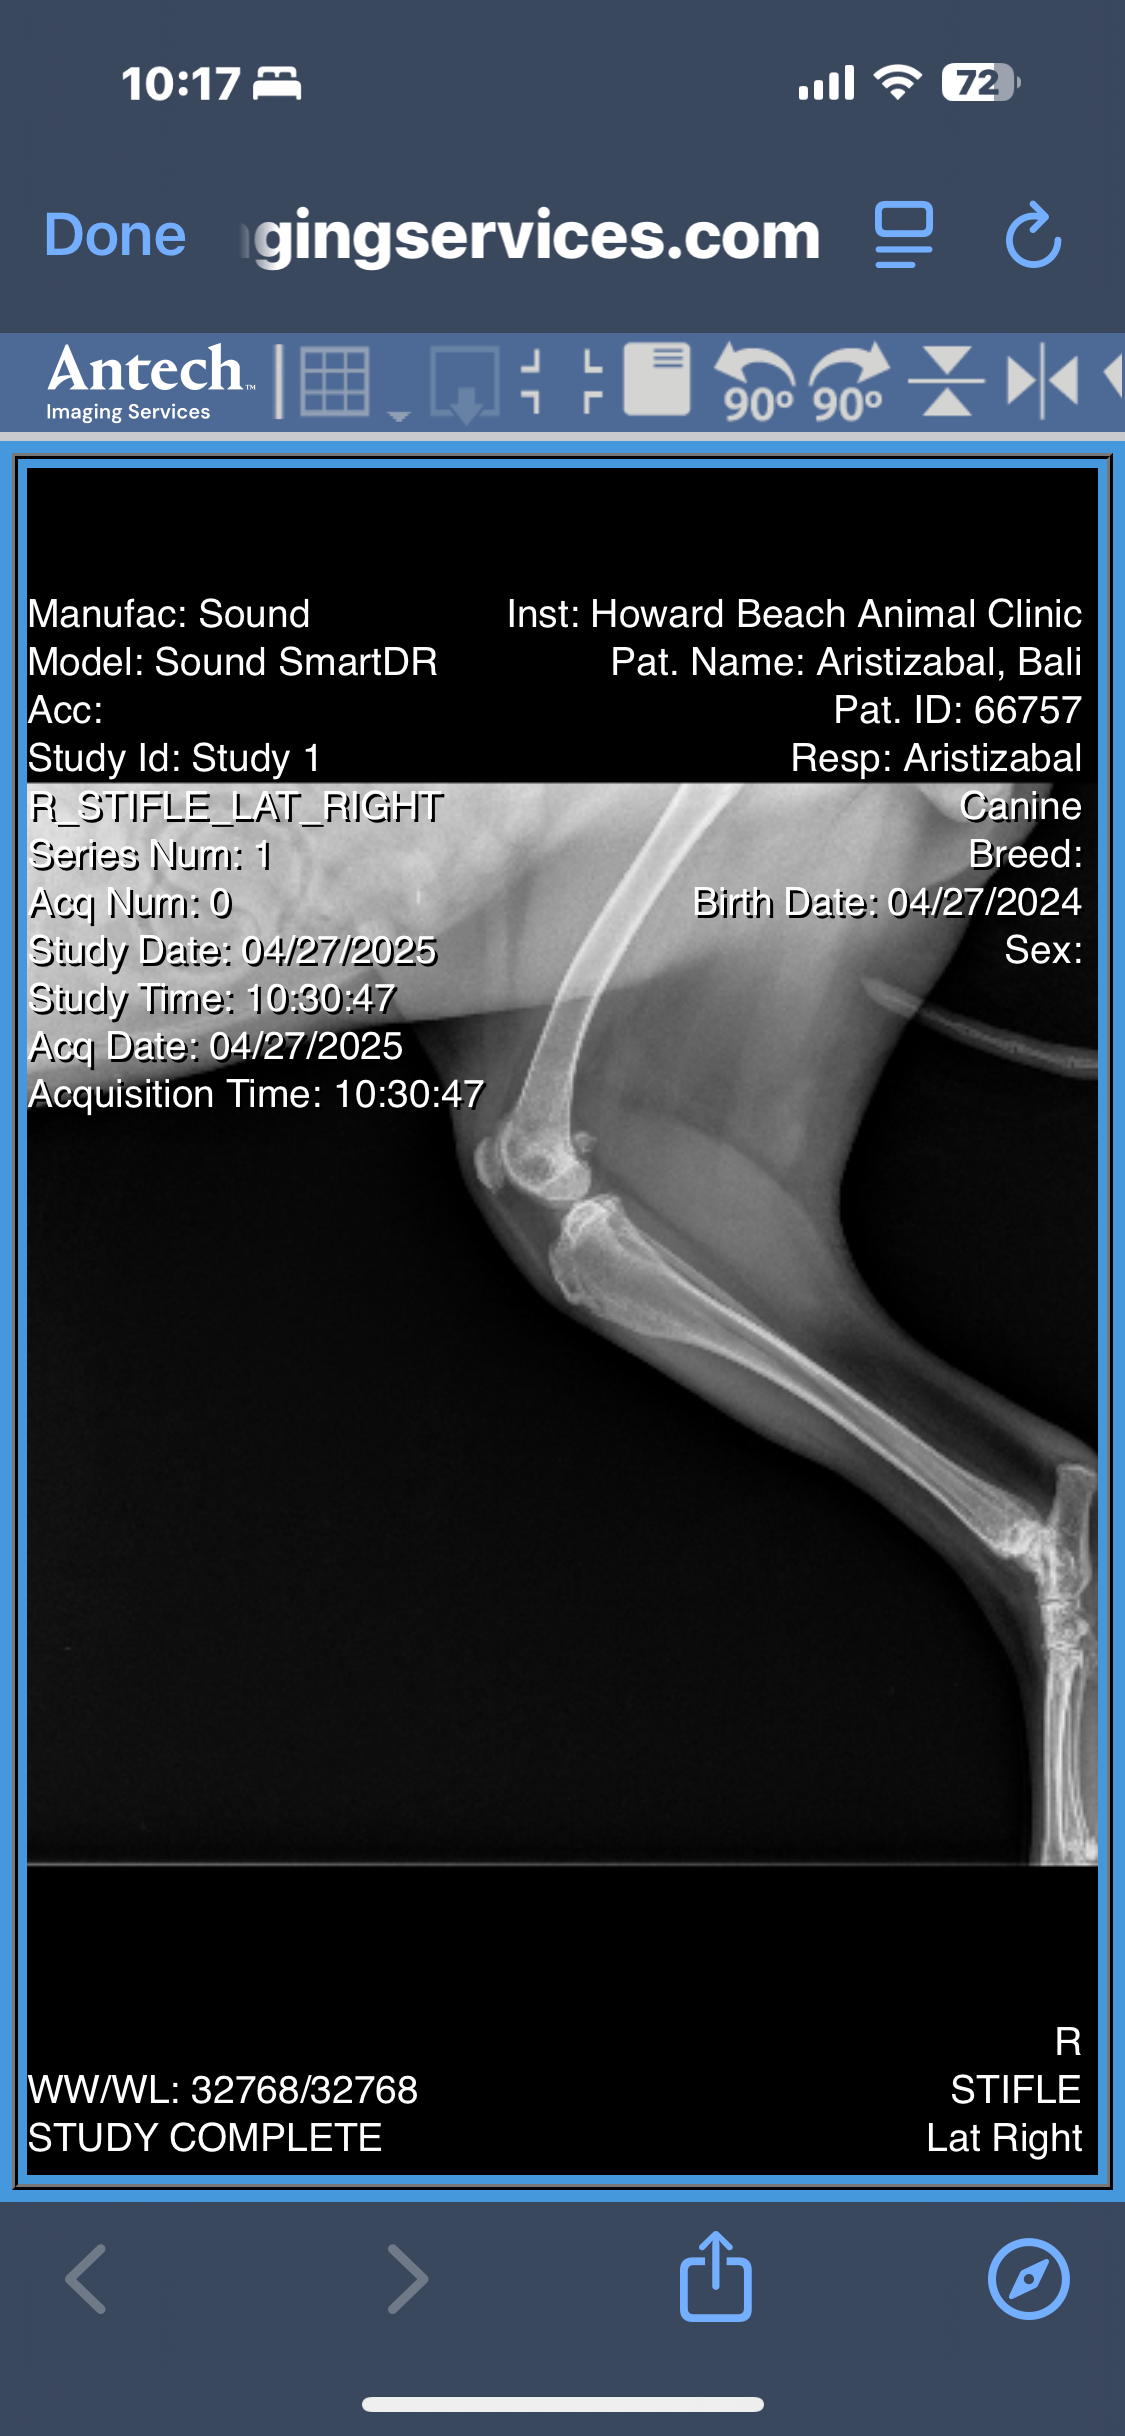

After months of limping, discomfort, and visits to the vet, Bali’s radiographs revealed multiple orthopedic issues:

• A minimally displaced fracture in her left femoral neck

• Severe bilateral hip dysplasia, more advanced on the left

• Osteoarthritis in both hips, with significant muscle atrophy

• Possible avascular necrosis of the femoral head or slipped femoral capital epiphysis

• And the concern of an underlying septic arthritis that hasn’t yet been ruled out